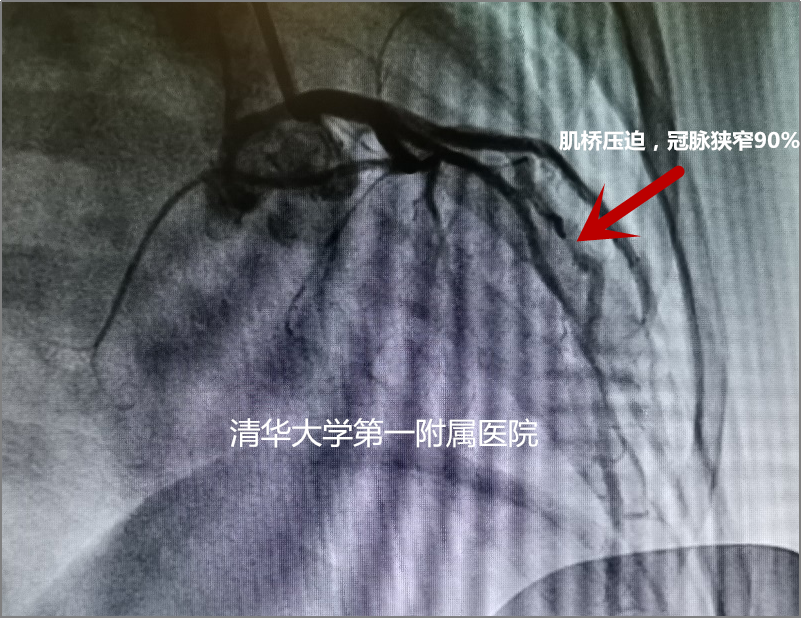

李小梅沉着冷静,通过仔细分析恩宝室速发作前后的心电图,发现他室速发作前先表现为心跳加速,同时心电图提示伴有心肌缺血,李小梅凭借丰富的临床经验,怀疑患儿存在冠脉肌桥。随后,心内科专家逯春鹏为患儿进行了冠状动脉造影检查。果然,结果显示为冠状动脉前降支近段肌桥,收缩期血管压缩90%。又一项诊断明确,离揪出患儿晕厥的“元凶”又近了一步!

冠状动脉造影检查结果